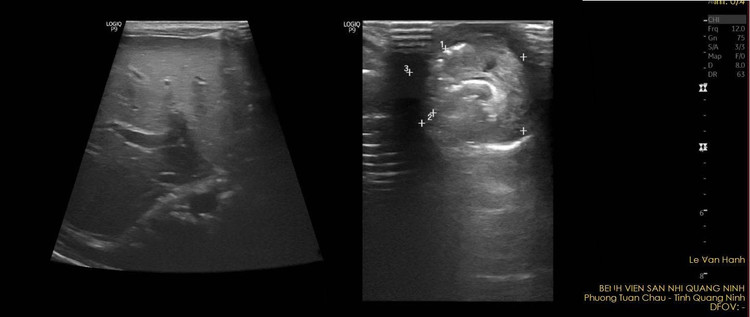

Kết quả khám và siêu âm ổ bụng cho thấy hình ảnh khối thoát vị, kích thước 21x22mm, thành phần trong khối là quai ruột có nhu động.

Hình ảnh khối thoát vị trên siêu âm - Ảnh BVCC